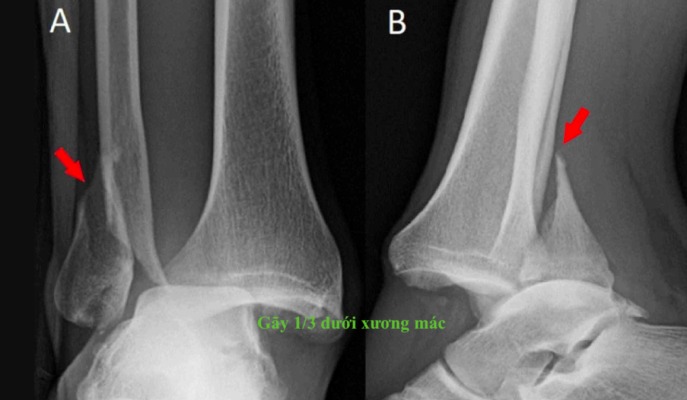

Gãy 1/3 dưới xương mác là một chấn thương thường gặp trong các tai nạn thể thao hoặc tai nạn giao thông. Mặc dù xương mác không phải là xương chính trong việc chịu lực của chân, nhưng nếu không được điều trị đúng cách, có thể dẫn đến các biến chứng không mong muốn. Vậy gãy 1/3 dưới xương mác có nguy hiểm không?

Gãy 1/3 dưới xương mác mặc dù không phải là một chấn thương quá nghiêm trọng như gãy xương đùi hay xương chày, nhưng nếu không được điều trị đúng cách, có thể dẫn đến các biến chứng nguy hiểm.

Gãy 1/3 dưới xương mác, nếu không kèm theo các biến chứng như gãy lệch hoặc ảnh hưởng đến các cấu trúc xung quanh, thường không gây nguy hiểm nghiêm trọng và có thể tự lành mà không cần phẫu thuật. Thời gian hồi phục của xương là khoảng 6 - 8 tuần, và mặc dù xương sẽ liền, quá trình phục hồi hoàn toàn trên phim X-quang có thể kéo dài đến 6 tháng. Tuy nhiên, trong suốt thời gian này, việc bảo vệ xương bằng nẹp và tránh va chạm, chấn thương là rất quan trọng.

Xương mác có khả năng tự lành trong thời gian từ 6 - 8 tuần, nếu người bệnh thực hiện đúng các chỉ dẫn và bảo vệ vùng bị thương. Tuy nhiên, phải lưu ý rằng, dù xương có thể lành và hồi phục chức năng, trên phim X-quang, hình ảnh lành xương hoàn toàn sẽ chỉ được thể hiện rõ sau khoảng 6 tháng. Điều này là do quá trình hồi phục và tái tạo xương cần thời gian để vững chắc và hoàn thiện.